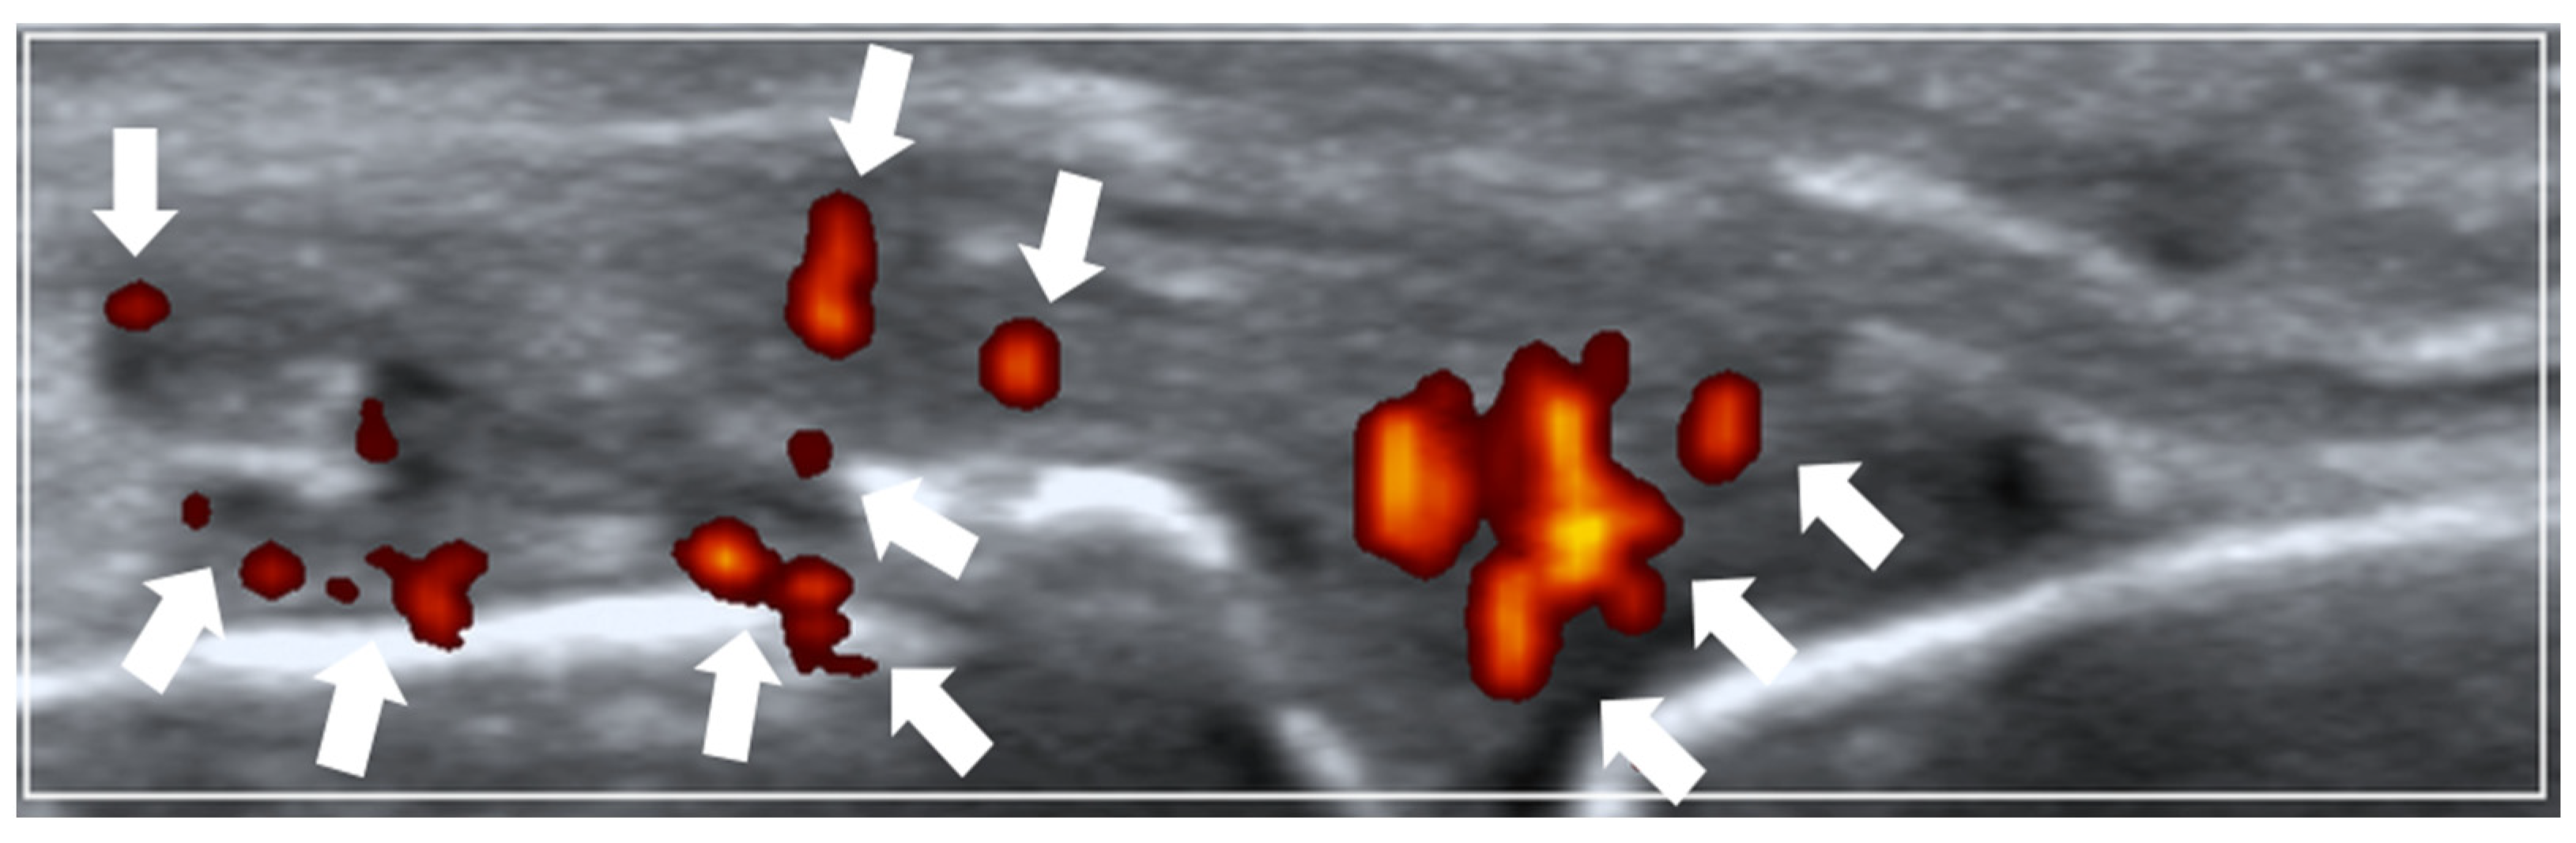

A 26-joint ultrasonography was performed based on the EULAR guidelines [23] at the following joint sites bilaterally: (1) dorsal recesses of all metacarpophalangeal joints (MCPJs), (2) dorsal recesses of the thumb’s interphalangeal joint and the remaining fingers’ proximal interphalangeal joints, (3) dorsal recesses of the wrist’s (i) distal radio-ulnar and (ii) radio-carpal/inter-carpal joints, (4) humero-radial and posterior fossa recesses of the elbow joint, and (5) supra-patellar recess of the knee joint. A single rheumatologist experienced in musculoskeletal ultrasonography carried out the ultrasound imaging. Thermal imaging was performed by a separate trained study team personnel while being blinded to the ultrasound findings. The Mindray M9 (Mindray Bio-Medical Electronics Co., Ltd., Shenzhen, China) ultrasound machine (with an L14-6Ns linear probe) was utilized with the following ultrasound scan settings: pulse repetition frequency (PRF) of 700 Hz and Doppler frequency of 5.7 MHz. Ultrasound PD joint inflammation severity was scored semi-quantitatively (0–3) according to the validated EULAR–Outcome Measures in Rheumatology (EULAR–OMERACT) ultrasound scoring method [24,25] (see Figure 1 for an example of scoring ultrasound PD joint inflammation).

Figure 1.

Ultrasound power Doppler (PD) joint inflammation. Example of a sonogram (longitudinal view) showing grade 2 PD joint inflammation at the metacarpophalangeal joint (arrows pointing towards PD vascularity).